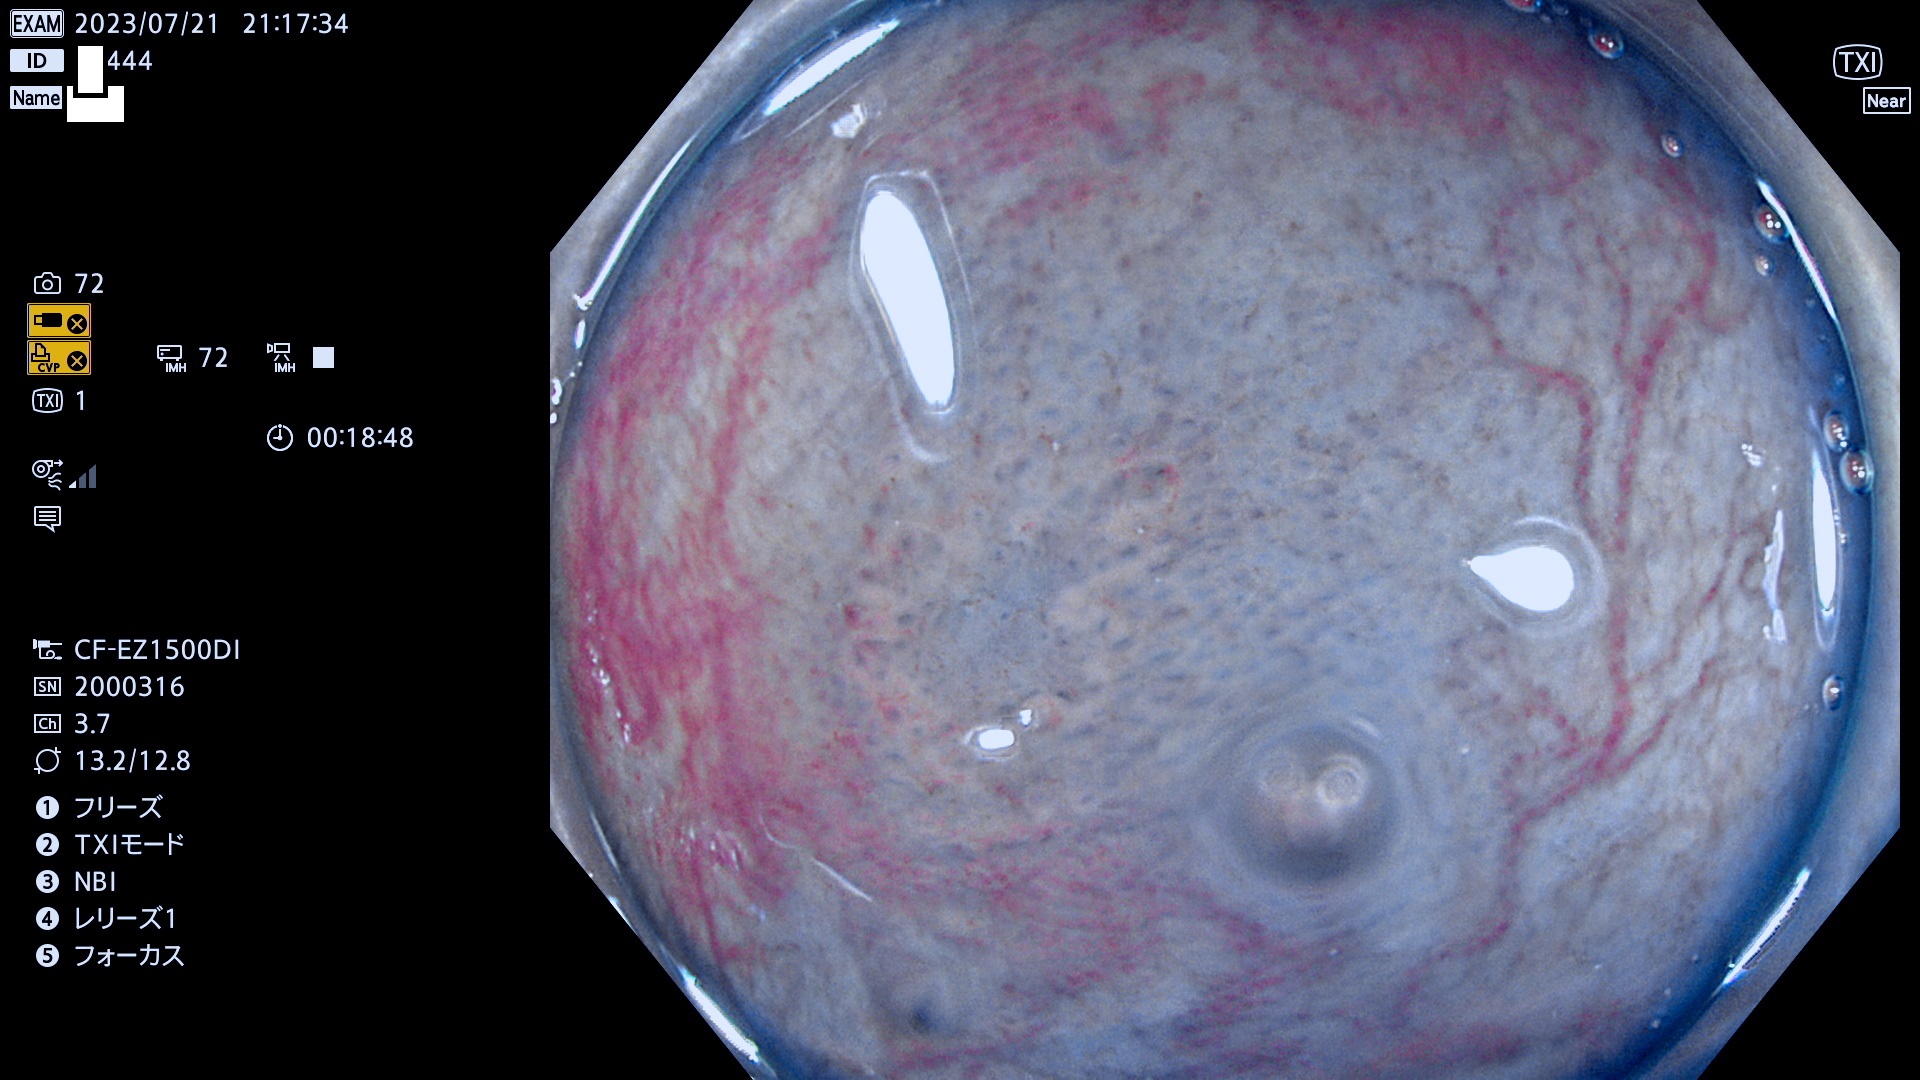

「表面型腺腫(Flat Adenoma)の中で、完全に平坦な物をUb、陥凹している物をUcと呼びます。平坦隆起型(Ua)よりも、発見が難しく危険な病変です。このタイプは「内視鏡後・大腸癌の重要犯人」であり、この発見率は「腺腫発見率」よりも、重要な意味があります。

抽出の対象期間 2023年7月20日(木)〜7月23(日)の4日間(48件の検査)12件